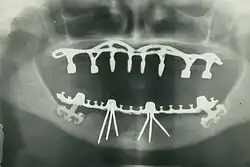

В настоящее время стоматология шагнула далеко вперёд. Стала возможной имплантация зубов и восстановление даже очень сильно разрушенного зуба, появились качественные пломбировочные материалы и современные инструменты для лечения зубов. При этом имплантация зубов возможна как при единичной потере зуба, так и при полном их отсутствии, для этого используют технологию вживления искусственного корня в костную ткань челюсти — зубных имплантатов, что даёт возможность восстановить сегменты зубного ряда зубными имплантатами без нарушения целостности и функциональности рядом стоящих здоровых зубов.